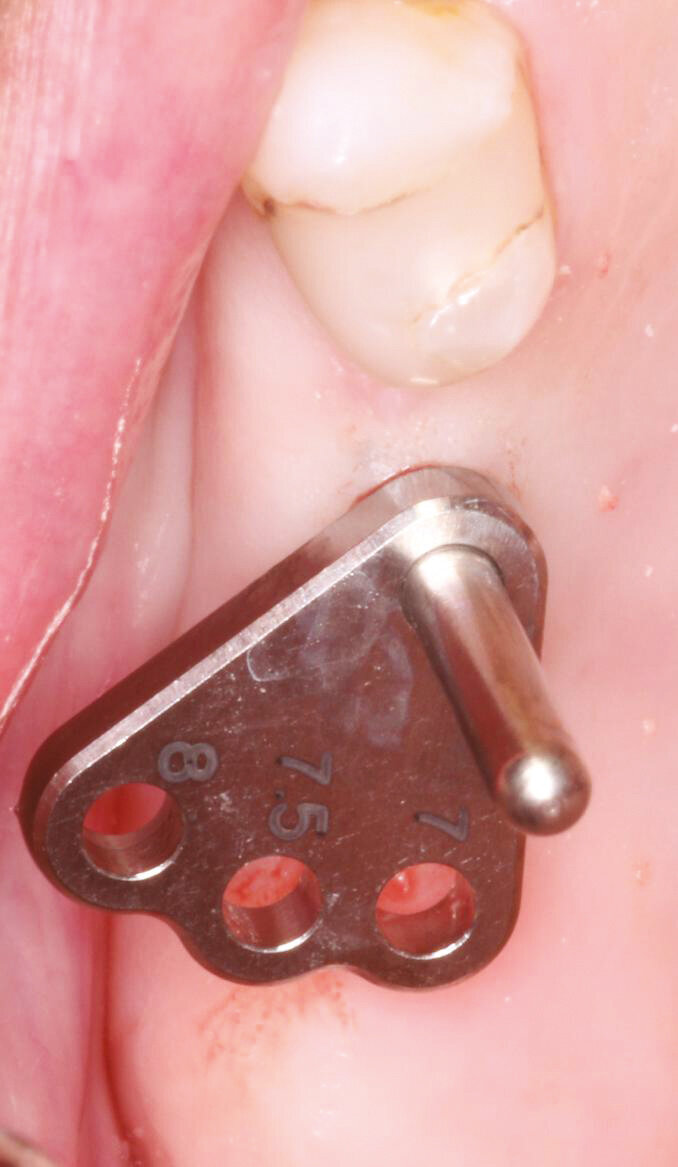

Fig.4: Parallel pin placed for verification.

Fig.8: Optimal inter implant distance with the Axiom placement guide.